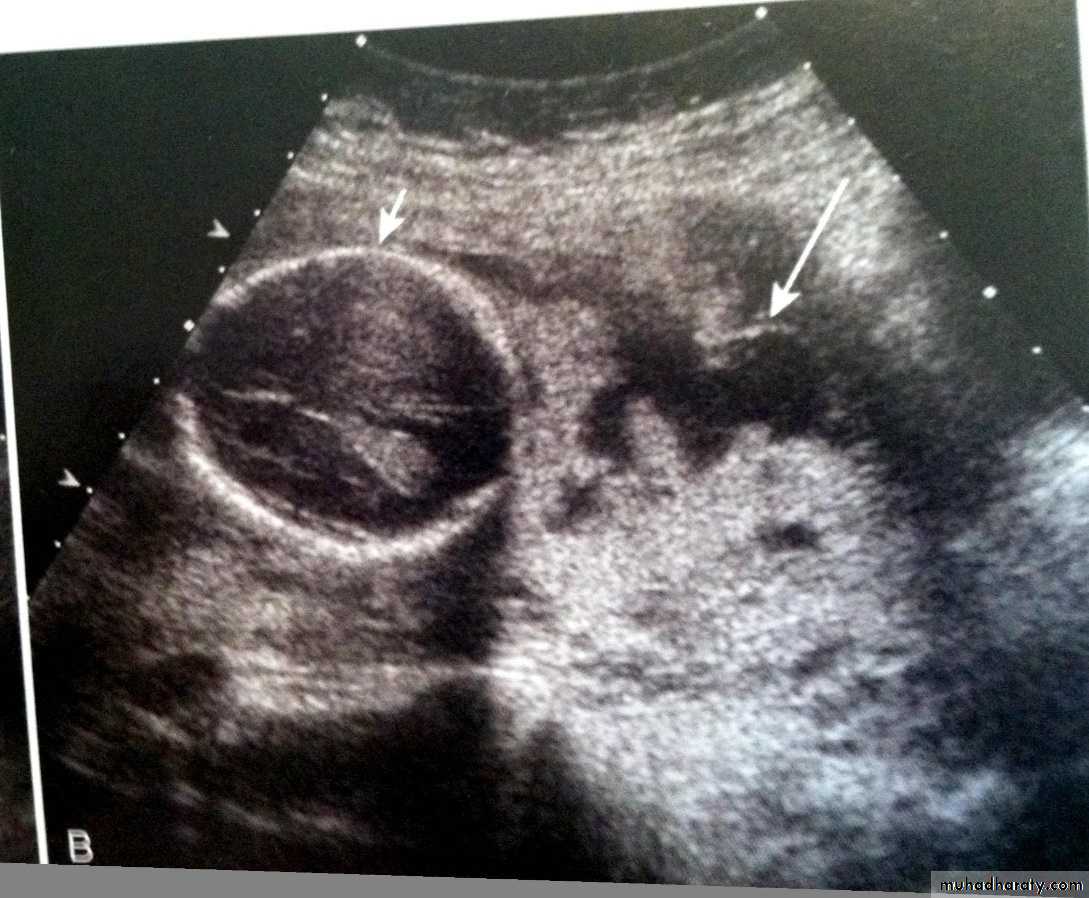

Ultrasonographysonohysterography may aid in the diagnosis of residual trophoblastic tissue.

transvaginal ultrasound for diagnosis

*the diagnosis is usually being made at laparotomy.*The diagnosis of placenta increta prior to delivery based on the lack of the sonolucent area normally seen beneath the implantation site during ultrasonographic examination is a finding confirmed in several reports.